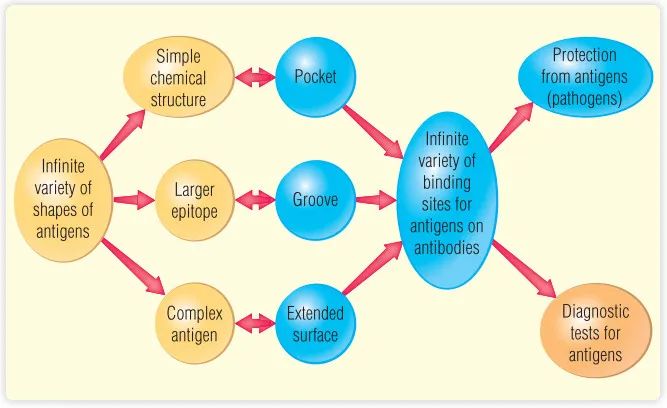

上图说明了本章的主题,它描述了抗体如何与几乎有无限种形状的抗原相互作用,以及这种相互作用如何保护我们免受病原体的侵袭。本章还回顾了抗原或抗体存在的非常特异的诊断试验的发展。抗体-抗原相互作用的最显著的特征是它们的特异性和亲和力。除此之外,抗体-抗原的相互作用很像其他受体-配体的相互作用。抗体与抗原之间的相互作用涉及物理化学力,类似于酶与其底物(或竞争性抑制剂)之间的相互作用,或受体(如胰岛素受体)与配体(如胰岛素)之间的相互作用。这些力来源于四个方面:(1)带电侧链之间的静电相互作用,(2)氢键,(3)范德华力,(4)疏水相互作用。

抗体非凡的特异性和亲和力使其在诊断测试中被广泛使用。本章的后半部分描述了抗体-抗原相互作用在诊断疾病中的几个最重要的应用。

许多实验方法已经被用来确定抗原-抗体结合位点的结构。到目前为止,最详细和最有价值的信息来自抗原-抗体复合物的X射线晶体学研究。通过对几种抗原-抗体复合物的三维结构的分析,得出的一个结论是,抗原结合位点的大小和形状可以有很大的不同。例如,结合部位可以是一个长而浅的缝隙,也可以是一个更宽、更开放的裂缝型结构(Fig 5.1)。对于小分子化合物,抗体上结合抗原的部位类似于酶活性部位。识别完整的较大蛋白质分子的抗体,它是针对表位的,抗原表位是蛋白质抗原的一部分-即抗体的结合位点-可能是突出的表面,而不是裂隙或缝隙(见Fig 5.1)。在所有情况下,抗原残基和抗体结合位点残基之间存在化学互补性。结合位点的壁由重链和轻链(VH和VL)的可变区(VH和VL)的氨基酸残基形成,称为高变区(HV区;见第6章)。抗体特异性源于抗原中的化学基团与抗体分子抗原结合位点上的化学基团之间的精确分子互补产生的。

Fig 5.1 抗原结合位点的大小和形状因其结合的分子或表位的类型而异